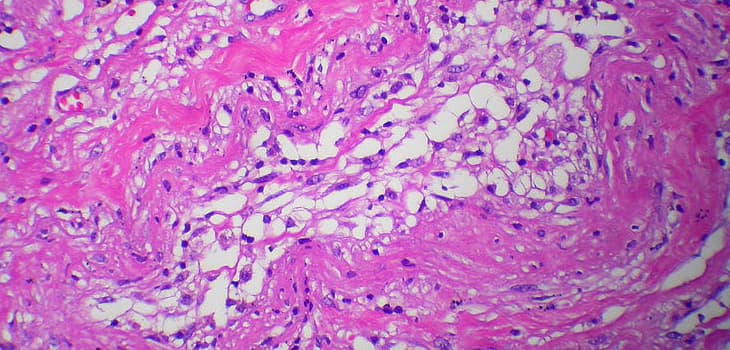

• Processing: adipose tissue is microfragmented and purified with patented Lipogems system.